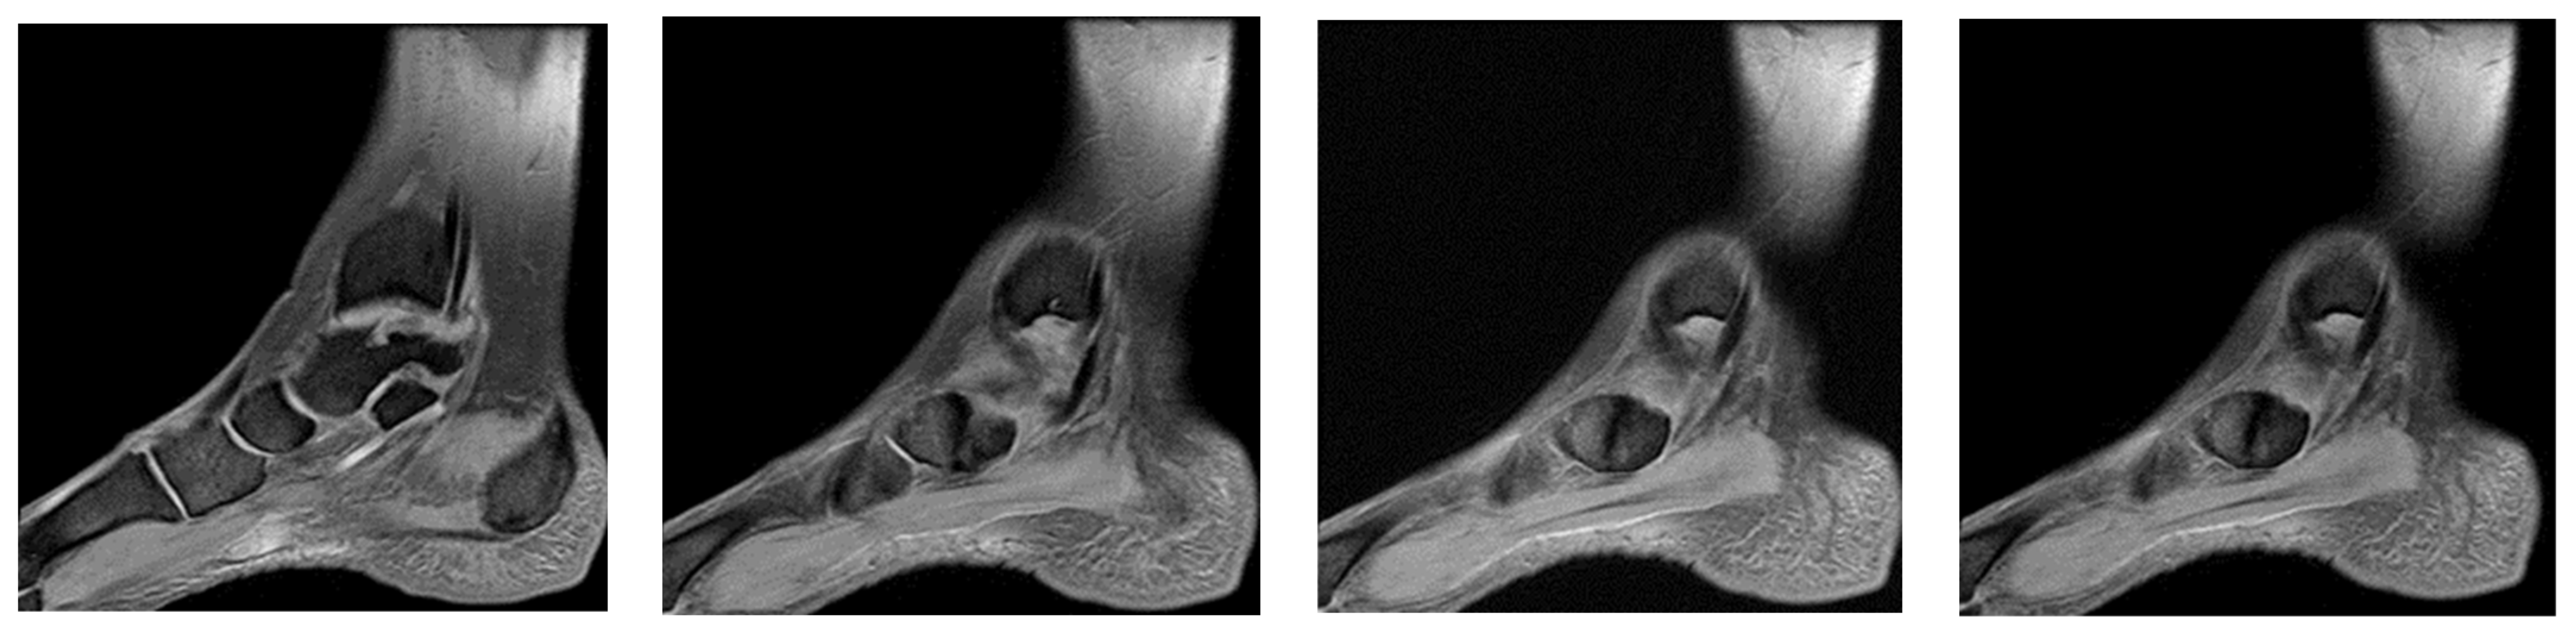

3.4. Case 4: Type III Accessory Navicular Impingement

A 26-year-old goalkeeper with a navicular injury, boasting six years of experience as a first-league professional in Romania, hails from an urban area and stands at 192 cm, weighing 95 kg. The latest case involves this goalkeeper, who, after sustaining a direct contact trauma during a match, reports experiencing pain and swelling in the dorsal part of his right forefoot. Forefoot X-ray diagnoses an improperly healed old right navicular fracture. As there was no trauma of the right foot, an MRI was performed, confirming the diagnosis of type III accessory navicular bone with impingement on the posterior tibial tendon.

Ankle MRI showed a well-delimited oval formation, at the posterior part of the navicular, with similar signals to the latter in T1 and T2 ponderations (bone formation), establishing certainty diagnosis of accessory navicular bone, excluding the suspicion of improperly consolidated navicular fracture/pseudoarthritis. STIR and PD fat sat sequences reveal hypersignal alterations in the posterior tibial tendon tangent to the accessory bone mentioned above, establishing the diagnosis of impingement syndrome with subsequent tendinopathy alterations (Figure 9, Figure 10 and Figure 11).

(a) Ankle MRI: sagittal stir acquisition, (b) ankle MRI: sagittal stir acquisition, (c) ankle MRI: axial T2 acquisition, (d) ankle MRI: sagittal T2 fat sat acquisition, (e) ankle MRI: coronal PD fat sat acquisition, (f) ankle MRI: coronal T1.

(a) Ankle MRI: axial T2 acquisition, (b) ankle MRI: axial T2 acquisition, (c) ankle MRI axial T2 acquisition.

Ankle MRI: sagittal T2 fat sat acquisition.

Excluding the improperly healed fracture of the navicular, the patient was treated as a contusion with functional rest, NSAIDs, analgesics, and physical therapy, which allowed the player to recover early and resume his competitive activity after 1 week.